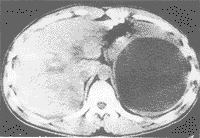

脾囊肿主要是由什么原因引起的

1.寄生虫性囊肿 由棘球绦虫属的包虫囊构成,由幼虫经血进入脾内发育生长成寄生虫性囊肿,囊内壁无衬覆上皮,囊内含寄生虫虫体或虫卵及坏死组织, 2%的棘球蚴病中可有脾包虫囊肿,常与肝、肺棘球蚴病并存,在我国北方畜牧地区可见。

2.非寄生虫性囊肿包括真性和假性囊肿

(1)真性囊肿:有表皮样囊肿、皮样囊肿、血管和淋巴管囊肿等,它与假性囊肿的区别在于囊内壁被覆扁平、立方或柱状上皮。其中表皮样囊肿多见于青年,常为单发性,最大直径可达31cm,囊内液体多达4000ml,色质浓稠,为淡红色或褐色,可有胆固醇结晶;病理形态可见,囊内壁衬以鳞状上皮,基底膜平整,无表皮钉突,无皮肤附属器。而表皮样囊肿来源不明,可能为胚胎期胃背侧系膜或中肾管的细胞误入脾内发育而成;其病理所见囊壁内衬鳞状上皮及附属器,为皮肤全层结构,可有神经组织及骨组织等,囊内可有白细胞、脂肪小体和胆固醇结晶。

(2)假性囊肿:较真性囊肿多见,约占非寄生虫囊肿的80%,囊肿多为单房性,可有外伤史,囊肿可以很大,囊壁无内皮细胞被覆。